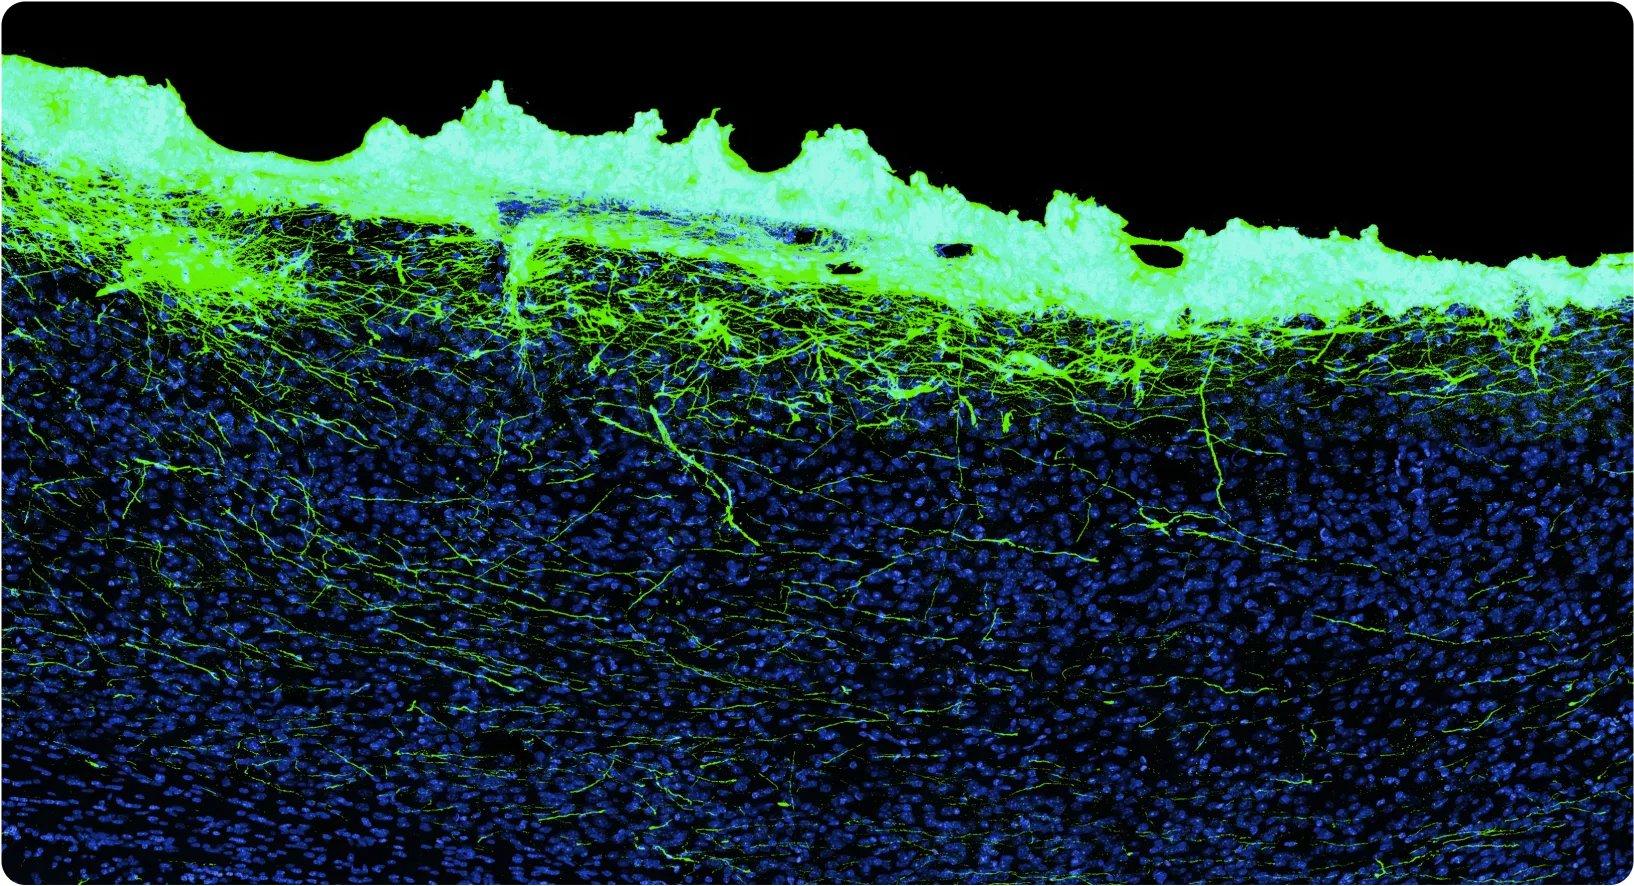

At Science, we’re developing a biohybrid probe technology using highly engineered, stem cell-derived neurons embedded in vitro in electronics and engrafted into the brain, forming new biological connections. The basic idea is pretty simple: since the brain is already largely composed of neurons, what happens if we add more neurons? The answer is they grow in and wire up extensively. Importantly, we solve the central problem described above by keeping the cell bodies with us, which is possible because we started with them. Only their axons and dendrites grow out into the brain, joining the representations they encounter.

There are a bunch of interesting benefits to this: the signal-to-noise ratio is great, so you can use smaller amplifiers and burn less power. Also, critically, you get chemical synapses, so you can imagine using neurons of various types — say some dopaminergic neurons, some acetylcholinergic neurons, some glutamatergic neurons — and then being able to “stimulate” using specific neurotransmitters. Since neurons form many connections, engrafting a million neurons (an easily practical device volume, far less than a cubic millimeter) might produce over a billion synapses; this is very far from thinking about things in terms of “channels” of electrodes. There is an immense amount of science to do here.